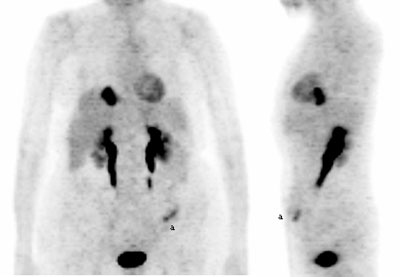

Fig. 2. - Imágenes coronal y lateral de tomografía por emisión de positrones de cuerpo completo. Mujer de 18 años en estudio por lesión naso-sinusal, donde se observa aumento del metabolismo de la [18]FDG en cerebro, área de musculatura oculomotora (a), musculatura cervical, paraclavicular y paravertebral. Asimismo se aprecia aumento del metabolismo de la [18]FDG en ventrículo izquierdo.. Volver